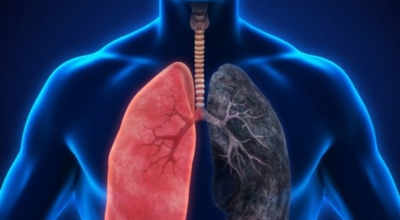

폐암의 공통 위험요소로 손꼽히는 이유가 되는 것으로 흡연이 있답니다. 흡연자는 비흡연자에 견주어 십몇 배는 더 폐암 발병확률이 높다고 하며 어느정도 기간 동안 흡연했는지에 따라 폐암 발생확률은 더더욱 더 높아져요. 흡연자라고 해도 금연을 하게 되면 폐암 발병확률이 가파르게 감소한다고 하니 폐암이 걱정되신다면 가장 먼저 금연은 필수입니다.

간접흡연 외에도 공사장과 같은 곳에서 미세먼지나 석면, 비소, 라돈, 카드뮴 등 신체에 옳지 않은 성분에 노출되는 환경적 요인으로 폐암이 발병할 수 있다고 하며 유전적 요인으로도 폐암이 발병할 수 있다고 해요. 가족 중 폐암을 앓았던 분들이 있다면 그렇지 않은 분들에 비교해 2배 가량 더 폐암에 걸릴 확률이 높다고 하는데요 이렇듯 폐암은 나도 모르는 새에 발병할 수 있으므로 자신의 신체 상태를 수시로 체크하여 폐암을 초기에 발견하는 것이 현명해요.